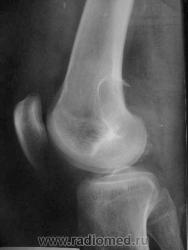

Здравствуйте, уважаемые коллеги! Сегодня в травмпункте принесли на описание снимки молодого человека 1984г.р. Травма, подвернул ногу. Жалобы характерные. Не наблюдался, не лечился. Прошу высказать мнение о характере патологии в метафизе бедренной кости.

Я склоняюсь к ГКО с кортикальным расположением, прорывом содержимого в мягкие ткани. А что думаете Вы? Т.к. снимок из травмпункта, поговорить с больным проблематично (я там совмещаю по вечерам).

какой красивый "козырек" по задней поверхности...

Расположение крупного очага деструкции эксцентрично (кзади) и вкрапления извести говорит в пользу солитарной хондромы, а местами нечеткие контуры ("скорлупа" теряется), "козырек" и  мягкоттканный компонент нацеливают на озлокачествление. Кроме того очень смущает структура прокс. эпиметафиза б/берц. кости. В любом случае, вижу прямые показания к активным действиям, начиная с биопсии.

И я за хондрому.

Спасибо за высказанные мнения. Интенсивная тень в проекции метафиза это артефакт на пленке. Больного я отправил на консультацию в специализированное учреждение, так что потеряться он не должен. Если узнаю результаты, то сообщу.